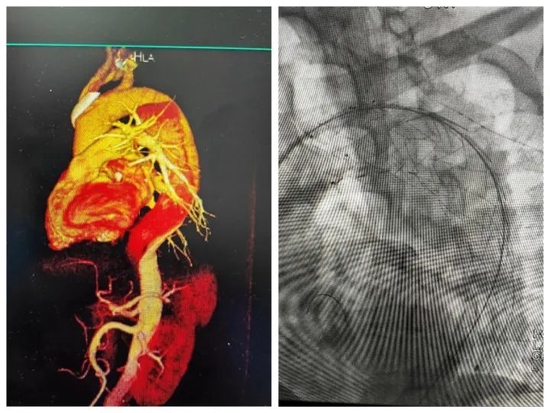

患者李某某,男,51岁,因“右侧肢体无力伴言语不清1天”,于8月17入住院,行颅脑CT示:双侧基底节区及大脑半球白质多发腔梗。头颅DWI示:双侧基底节区新发梗死灶。胸部CT示:双肺坠积性改变;降主动脉局部管径增宽。主动脉全程CTA扫描提示:主动脉夹层。遂转入心内科四病区进一步治疗。该患者既往有高血压病史,且血压控制极差,动脉瘤随时有破裂风险,一旦瘤体破裂,患者几乎无生还可能。我院心血管病院张誉洋院长,心内四病区葛兴利主任医师、李同华主任、王博副主任医师详细查看了患者的主动脉CTA影像及其他辅助检查后,认为该患者属于Stanford B型主动脉夹层,必须及时手术治疗。

由于患者同时合并新发脑梗死,手术风险大,技术难度高,我院专家们术前进行了多次认真讨论,设计出最佳手术方案,并制定了详细的术前、术中、术后风险情况应急预案。今日中午,在国际医学中心李滨教授和西安交大一附院刘亚民教授共同指导下,张誉洋院长带领心血管内科四病区介入团队历时2个小时的精准操作,成功实施了我院首例胸-腹主动脉夹层动脉瘤覆膜支架腔内隔绝术。术中造影清晰显示患者内膜破口,通过股动脉送入支架推送器,将主动脉覆膜支架精准置入破口位置,达到100%覆盖。术后造影显示支架位置良好,手术达到满意效果。